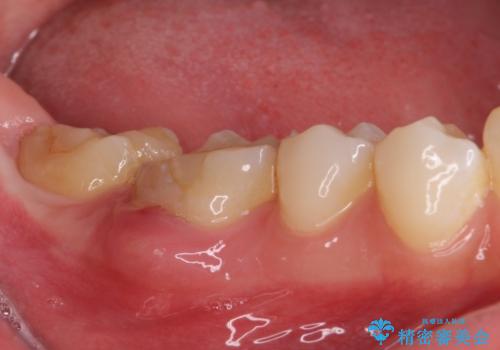

根管治療の必要な歯がいくつかあるため、まずは根管治療を行い、その後インビザラインにて矯正治療を行うこととしました。

矯正治療後に前歯をセラミックブリッジに、奥の銀歯はセラミックインレーやPGAインレー(ゴールドインレー)にて補綴・修復治療を行うこととしました。